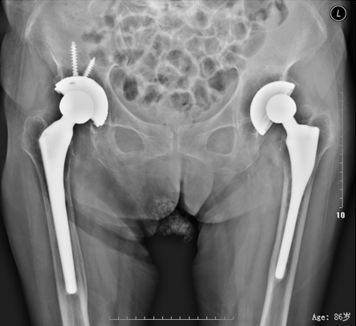

45岁,女性患者,2010年4、5月前于外院行分别行双侧全髋关节置换术,术后1年开始出现双髋轻微疼痛,未予系统诊治;2014年3月来我院就诊,只能卧床,被动强迫体位,双髋活动严重受限,X片如上。

诊断为双侧人工髋关节假体周围感染,于2014年4月分别行双侧髋关节假体取出、病灶清理、抗生素骨水泥占位器旷置术

感染控制后于2014年7月、8月分别行左、右侧复杂髋关节翻修术(Spcer占位器取出,钛网固定、打压植骨、翻修假体植入,右侧联合使用大粗隆钢板)。术后4年复查照片如上,打压植骨血管化,髋关节假体稳定,位置角度良好,患者功能恢复良好。